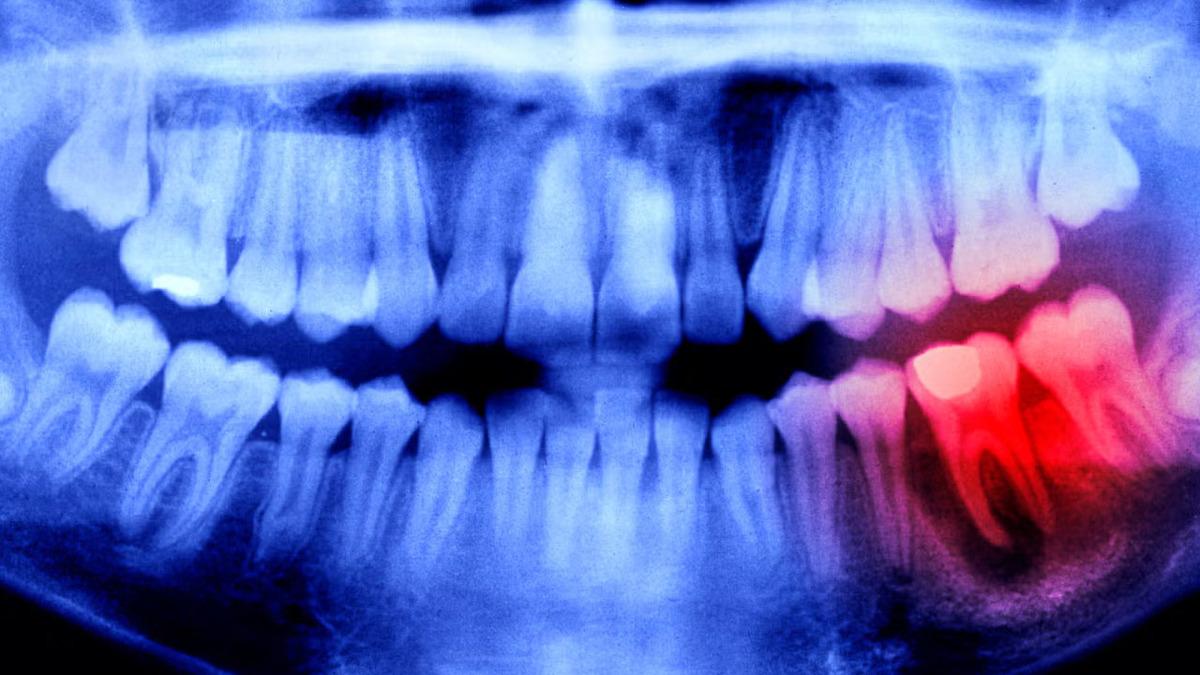

Japonya’da çalışmalarını sürdüren bilim insanları, insanlık için çok önemli olan bir çalışmayı noktalamak üzereler. Eğer bu çalışma istenildiği gibi tamamlanabilirse insanlar, diş kaybı sorunu yaşamayacaklar. Uygulanacak bir ilaç tedavisi, yeni dişlerin çıkabilmesini sağlayacak. Peki bu nasıl mümkün olacak?

Dişler, yapıları gereğince kemiklerle aynıdırlar. Ancak kemiklerin aksine dişlerin kendini yenileme, kırılma hâlinde onarım gibi bir özellikleri yoktur. İşte Japon bilim insanları, geçmişten gelen bilgi birikimini de kullanarak bu duruma bir çözüm ürettiler. Bilim insanları, 2030 yılı itibarıyla ilacı genel kullanıma açacaklarına inanıyorlar.